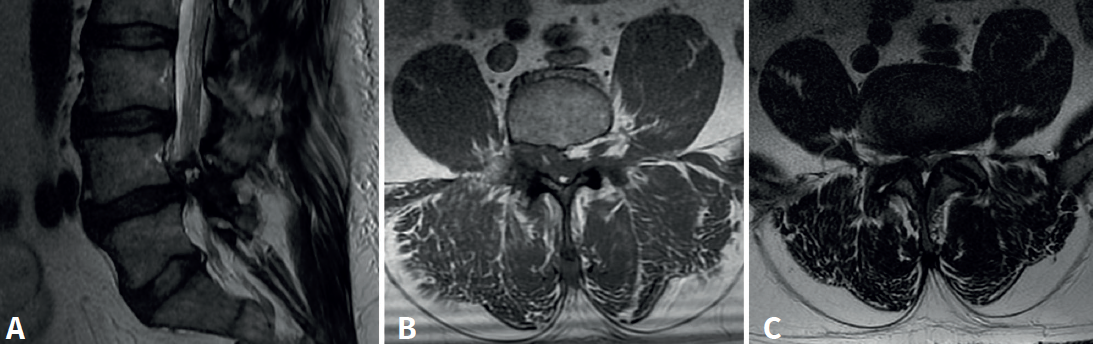

Se trata de un varón de 57 años, empleado en recogida de basura. Diez días antes de la consulta sufre una caída accidental con dolor intenso en el miembro inferior izquierdo, hipoestesia en calcetín y debilidad para la flexión y extensión del tobillo. En la exploración física presentaba Lasègue izquierdo negativo, derecho positivo a 50° y femoral stretch test derecho positivo. Se constató fuerza 1/5 en el tobillo izquierdo. La resonancia magnética (Figura 1) mostró discopatía L4-L5 con hernia discal posteromedial derecha. La electromiografía (EMG) evidenció afectación radiculoplexular izquierda moderada L3-L4 y grave L5-S1 posganglionar.

Figura 1. Resonancia magnética lumbar inicial. A: corte sagital en secuencia T2: discopatía de grado IV en L4-L5 con hernia discal extruida; B: corte axial en secuencia T1 a nivel de L4-L5, con estenosis del receso lateral derecho secundaria a extrusión discal; C: corte axial en secuencia T2, con protrusión discal difusa con estenosis foraminal bilateral y canal medular estrecho (grado C según Schizas-Theumann).